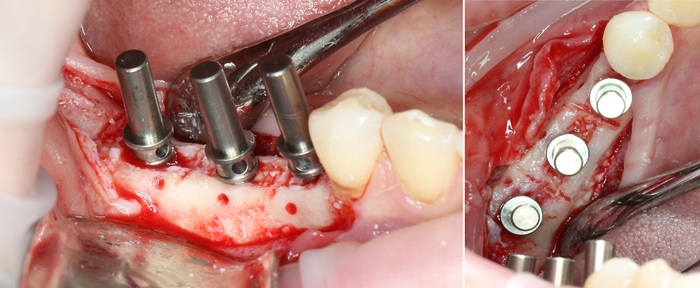

Уже на следующий день была запланирована имплантация.

Дабы не перегружать вас обилием одинаковых картинок, я оставлю один рентгеновский снимок, но отмечу, что установка имплантатов на верхней и нижней челюсти проводилась с разницей в 10 дней.

На верхней челюсти было дополнительно удалено два боковых резца с одномоментной установкой имплантатов, так же они были установлены в области четверок и шестых зубов. Дополнительно было проведено наращивание костной ткани - двусторонний синус - лифтинг. О том, что это такое, можно почитать ТУТ и ТУТ.